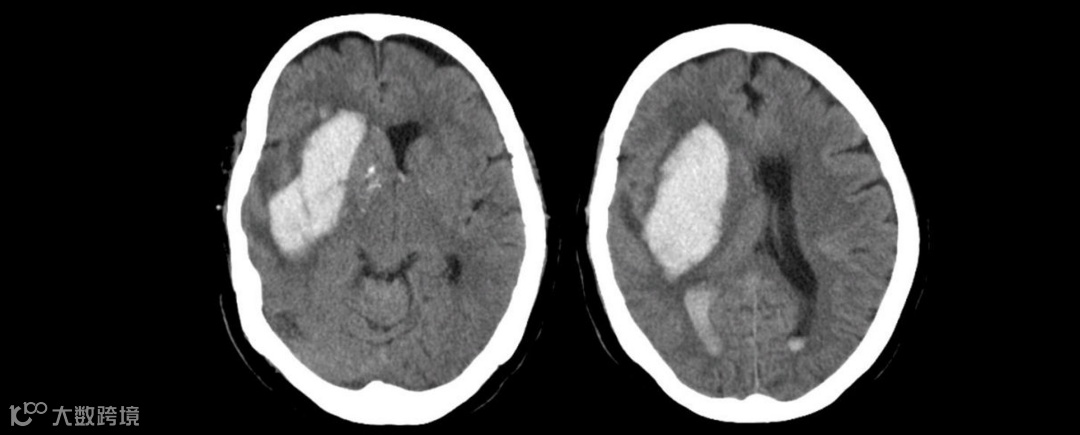

现病史:入院2天前,患者于“XX医院”住院时无明显诱因出现发热,测量体温最高42.0℃,伴寒战,恶心、呕吐,呕吐物为胃内容物。予退热药,仍反复发热,呼吸急促,间断四肢强直,行“肺泡灌洗液”NGS检查检出“金黄色葡萄球菌、鲍曼不动杆菌、白念珠菌”(图1),CT提示双下肺坠积性肺炎(图2),血常规提示血象高、血小板低,给予“万古霉素、比阿培南”抗感染治疗。1天前出现心率快、血压低,尿量减少,血小板极低,为进一步诊治,转入我院就诊。以“脓毒血症”经急诊收入我科。

既往史:8月前(2022-12-09)因“右侧基底节区脑出血破入脑室”,于当地医院性“去骨瓣减压术”(图3),术后四肢瘫痪、植物状态。1月余前(2023-06-07)于“北京XX医院”行“脑刺激器”植入术。

图3. 8月前外院头颅CT检查

图4. 入院前外院复查头颅CT